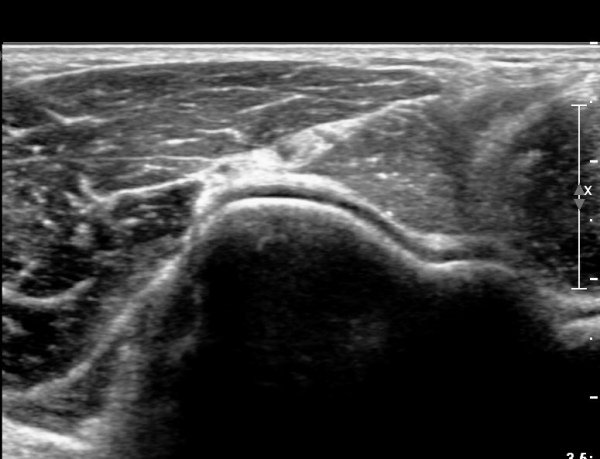

ŽÃËÀÚ¸¦ Á¶±Ý ´õ À̵¿ÇÏ´Ï Èİñ°£ ½Å°æÀÇ ºÎÁ¾ÀÌ ´Ù½Ã °üÂûµÈ´Ù(»çÁø 3).